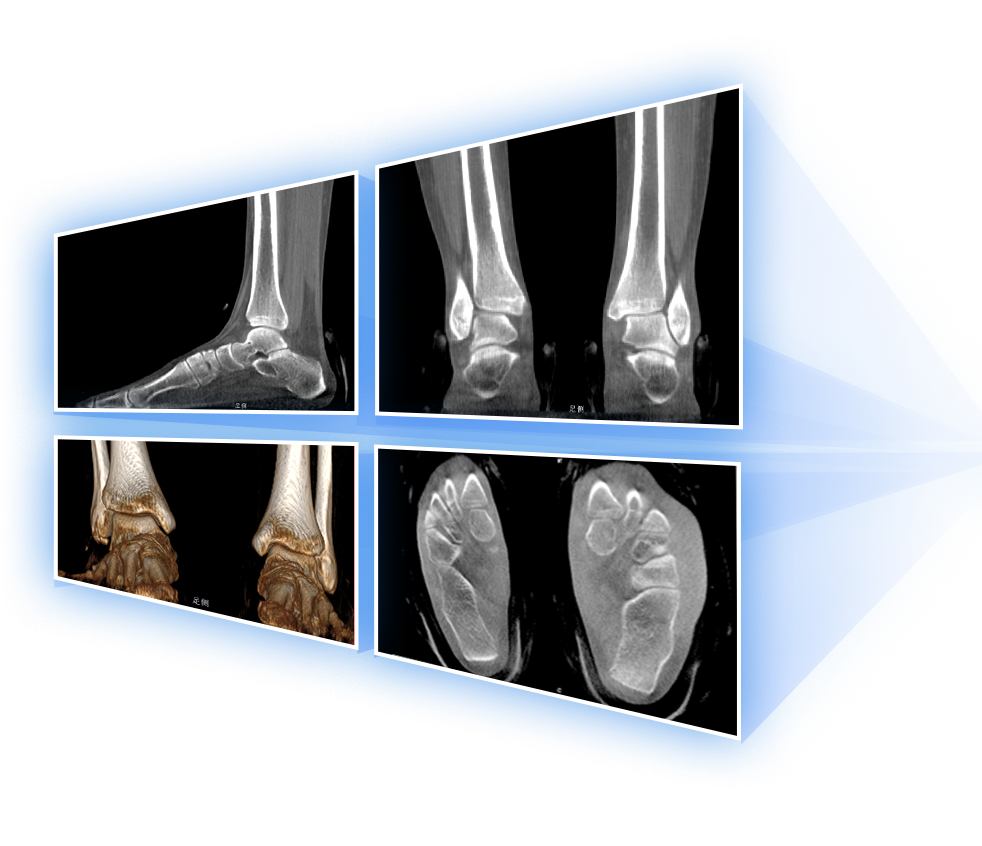

足踝

精準診斷

手術方案規劃

術后隨訪

VR體繪制重建